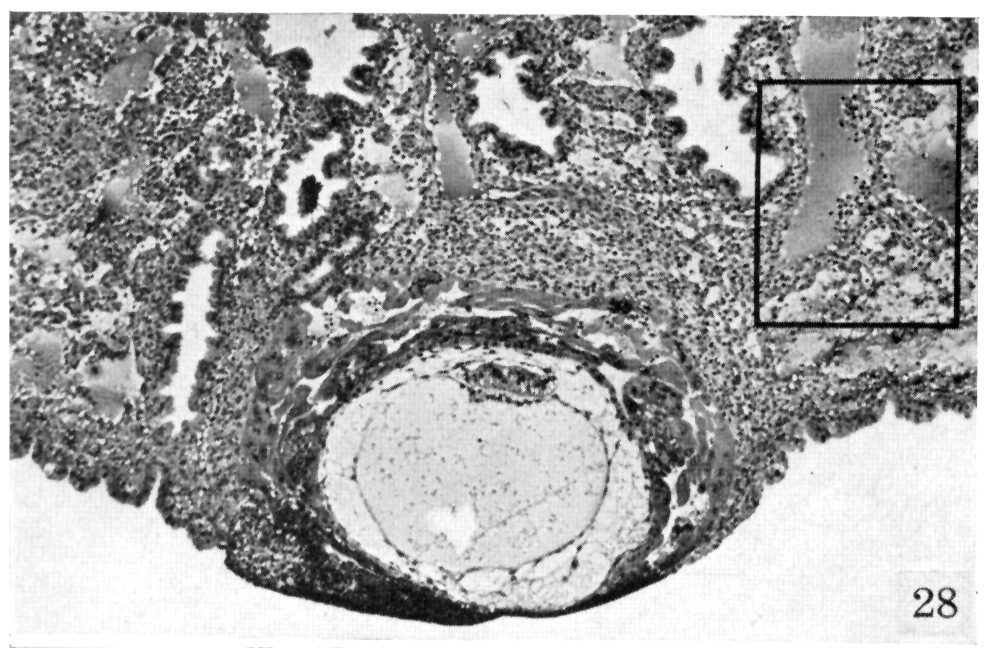

A low-power view to show the orientation of the embryo to the large arteriovenous sinusoids supplying blood to the trophoblast lacunae. The rectangle encloses the sinusoid seen more in detail in figure 29.

Fig. 28. Hertig and Rock, 1941.